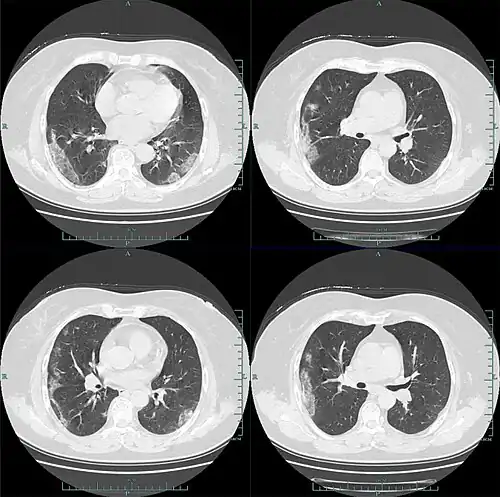

W badaniu 1099 chińskich pacjentów za pomocą tomografii komputerowej stwierdzono zmiany w płucach typu mlecznej szyby w 56% przypadków. Zmian w badaniu radiologicznym nie wykazano u 17,9% pacjentów z łagodną postacią choroby oraz u 2,9% pacjentów z ciężką postacią choroby. Limfopenia była obecna u 83,2% przyjętych pacjentów. 5% pacjentów zostało przyjętych na oddziały intensywnej terapii, 2,3% wymagało mechanicznego wspomagania wentylacji płuc, a 1,4% zmarło[39]. Według zespołu badawczego Bernheima obustronne i obwodowe zacienienia w płucach typu mlecznej szyby są najczęstszymi objawami widocznymi na skanach tomografii komputerowej. Konsolidacje miąższu płucnego, liniowe zacienienia płuc oraz objaw odwróconego halo to inne typowe symptomy widoczne w obrazowaniu radiologicznym. Początkowo zmiany są widoczne w jednym płucu, jednak – wraz z rozwojem choroby – u 88% pacjentów stają się obecne w obu płucach[40]. Dzieci zdają się przechodzić chorobę lepiej niż dorośli i występują u nich łagodniejsze objawy, jednak brakuje wciąż danych, aby stwierdzić to jednoznacznie[41].

Zmiany w diagnostyce obrazowej u pacjentów obejmują najczęściej[47][50][55]:

- obustronne i obwodowe zacienienia w płucach typu „mlecznej szyby”

- niejednolite konsolidacje miąższu płucnego

- liniowe zacienienia w płucach

- objawy odwróconego halo

- predylekcję do występowania zmian w tylnych segmentach lub płatach dolnych